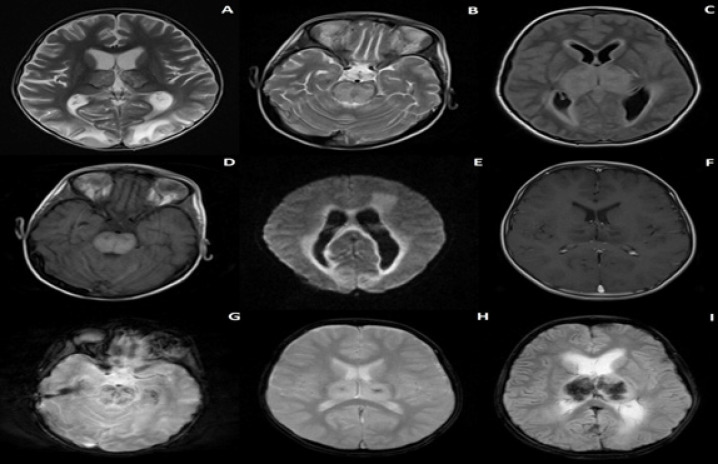

Objectives: Acute necrotizing encephalopathy of childhood (ANEC) is a rare, potentially life-threatening condition. This study aimed to identify clinical profiles and outcomes of ANEC while assessing the accuracy of severity scoring in the Iranian population.

Materials & methods: The present study collected demographic, clinical, laboratory, and radiological data from children diagnosed with ANEC. Severity was measured using the ANE-Severity Score (ANE-SS), while outcomes were assessed with the Glasgow Outcome Score (GOS). This research analyzed the relationship between these scores and various parameters for statistical significance.

Results: Seven patients were included over three years, with an average age of 4.4±2.7 years (5 males). ANE-SS varied from moderate to high, with most patients experiencing moderate to severe disabilities, as indicated by the GOS. Significant correlations were found with initial serum magnesium levels, pupil light reactivity, and initial GCS score (P-value < 0.05).

Conclusion: Controlling initial magnesium levels may improve ANEC outcomes. Additionally, intact pupil light reactivity at admission was associated with a better prognosis.